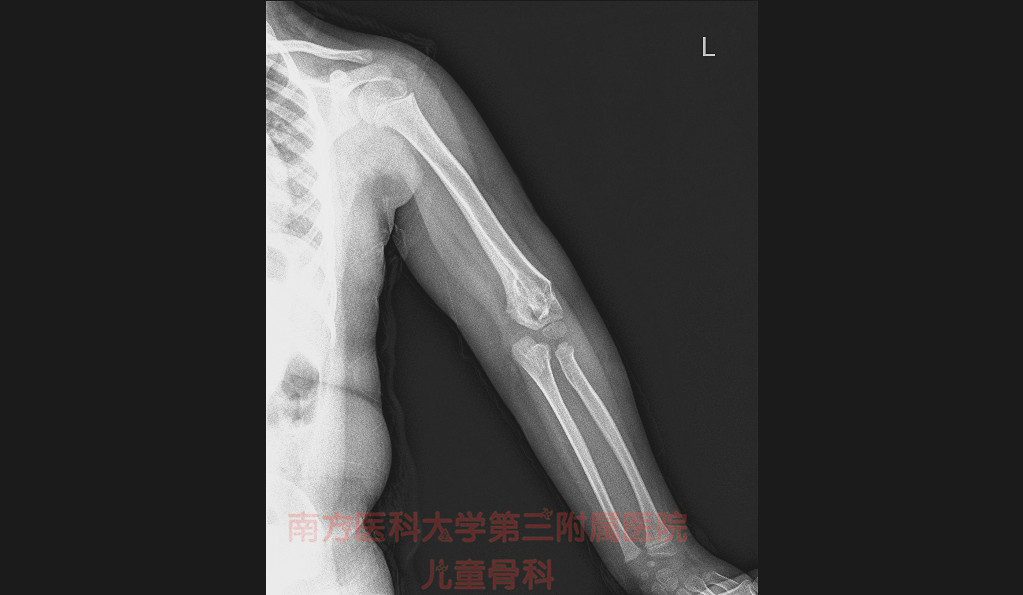

小徐跟婆婆又吵了一架,气愤地夺门而出,带上孩子来医院看病。我让孩子手臂伸直,一看,已经肘内翻挺严重的。

跟小徐沟通后,我了解到孩子之前因摔倒致左肱骨髁上骨折,这种情况应该是骨折后复位不良引起的肘内翻畸形。

其实,左肱骨髁上骨折特别容易发生骨折的畸形愈合,最常见的就是肘内翻。正常情况下我们的肘关节会有个向外的角度,也就是医学上所说的“携带角”。但是肱骨髁上骨折的出现了畸形愈合,如肘内翻时,外观上看上去是“胳膊肘向里拐”,影响外观,严重者影响肘关节的伸屈活动,对日常生活造成一定的影响。并且肘内翻也会增加肘关节再次发生骨折的风险。同时肘关节周围的神经血管在骨折发生显著移位时发生损伤。但是主要治疗得当,并且配合术后功能锻炼一般不会出现这种情况。

如果因为骨折的畸形愈合导致肘内翻了,和健侧相比,两侧不对称的角度超过15°可能需要进行手术矫正,一般在骨折完全愈合,锻炼结束后,大概伤后半年时间就可以考虑矫形。#清风计划# #春季养生正当时# @头条健康联盟 @儿科医生雨滴 @普外科曾医生